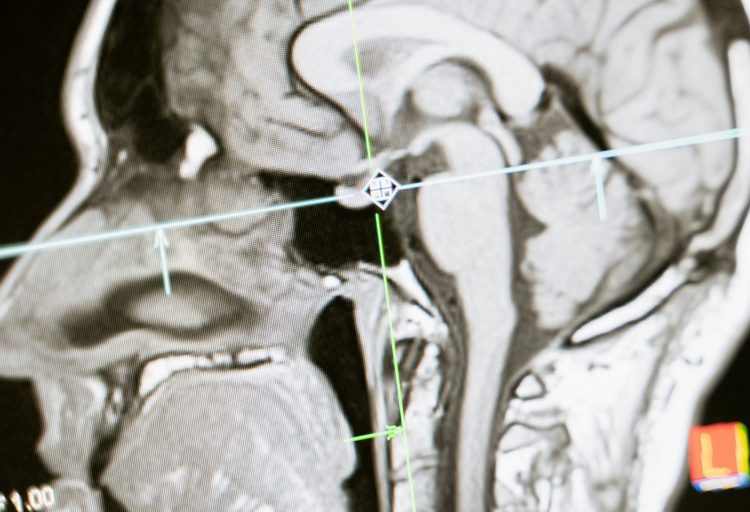

Wirbelsäulenbeschwerden sind wie eine Eintrittskarte für Schwindel. (Foto: hkgoldstein0 – pixabay.com)